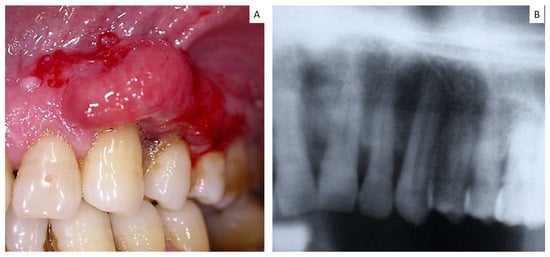

| 17 | 70 | F | Maxillary gingiva Around dental implant | Small cell carcinoma | n.a. | Yes |

| 18 | 62 | M | Maxilla gingiva Around dental implant | Adenocarcinoma | n.a. | Yes |

| 20 | 72 | F | Maxillary gingiva | Adenocarcinoma | n.a. | Yes |